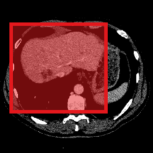

Consider a three-dimensional object within a volume. It is straightforward to produce a 3D bounding box of the object by finding its extreme points in the three coordinate axes. While this 3D bounding box will be tight in the 3D sense, its rectangular cross-sections will not, in general, remain tight with respect to the planar cross-sections of the volume. Fig. 1 illustrates such a case for the task of liver segmentation in a CT volume. In the Experiments section we show that the success of existing 2D weakly-supervised segmentation methods relies on the bounding boxes being tight and therefore the tightness of the individual 2D bounding boxes should be corrected before training and applying a segmentation CNN.

The global bounding box tightness prior mentioned above assumes that each of side of the box is sufficiently close to the target region. This means that for any region shape, each vertical or horizontal line inside the bounding box will cross at least one pixel belonging to the target region. This condition does not hold when the provided annotation comes as a 3D bounding box which is represented as a series of per-slice non-tight 2D bounding boxes. In this case, there will exist vertical or horizontal lines shown as stripes in Fig. 1 (d), that will lie outside of the actual object boundary. In the Experiments section we demonstrate the poor performance of the weakly-supervised approach from [5] when the user-provided bounding box is much wider than the true object of interest.